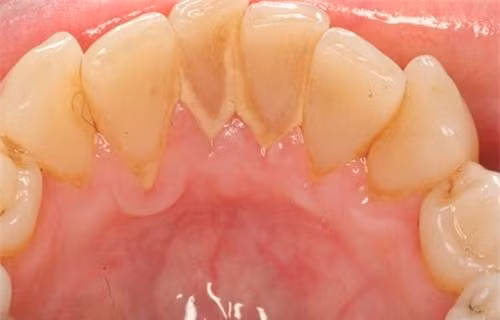

Cao răng (hay vôi răng) là mảng bám đã được vôi hóa bởi hợp chất muối calcium phosphate trong nước bọt. Thông thường mảng bám cần tồn tại trong miệng khoảng 1 tuần để biến thành cao răng. Vì vậy, nếu chúng ta làm vệ sinh răng miệng kĩ và thường xuyên thì cao răng sẽ không còn cơ hội hình thành.

Cao răng thường tập trung ở cổ răng, có màu trắng đục, ở những người hút thuốc lá thì cao răng nhuộm màu vàng nâu, gây mất thẩm mỹ.

Cao răng có 2 loại là cao răng thường và cao răng huyết thanh. Cao răng thường như đã mô tả ở trên, khi cao răng thường gây nên viêm lợi tại chỗ, lợi vùng viêm đó sẽ tiết dịch viêm và chảy máu, máu đó ngấm vào cao răng thường tạo nên màu nâu đỏ, lúc này mảng cao răng đó được gọi là cao răng huyết thanh.

Tốc độ tạo cao răng ở mỗi người một khác, sự hình thành của nó bị ảnh hưởng của những thành phần có trong nước bọt, thói quen ăn uống, thói quen vệ sinh răng miệng. Sau khi đánh răng sạch khoảng 48 giờ là thời gian hình thành cao răng nhanh nhất, cao răng có màu nâu hoặc đen.